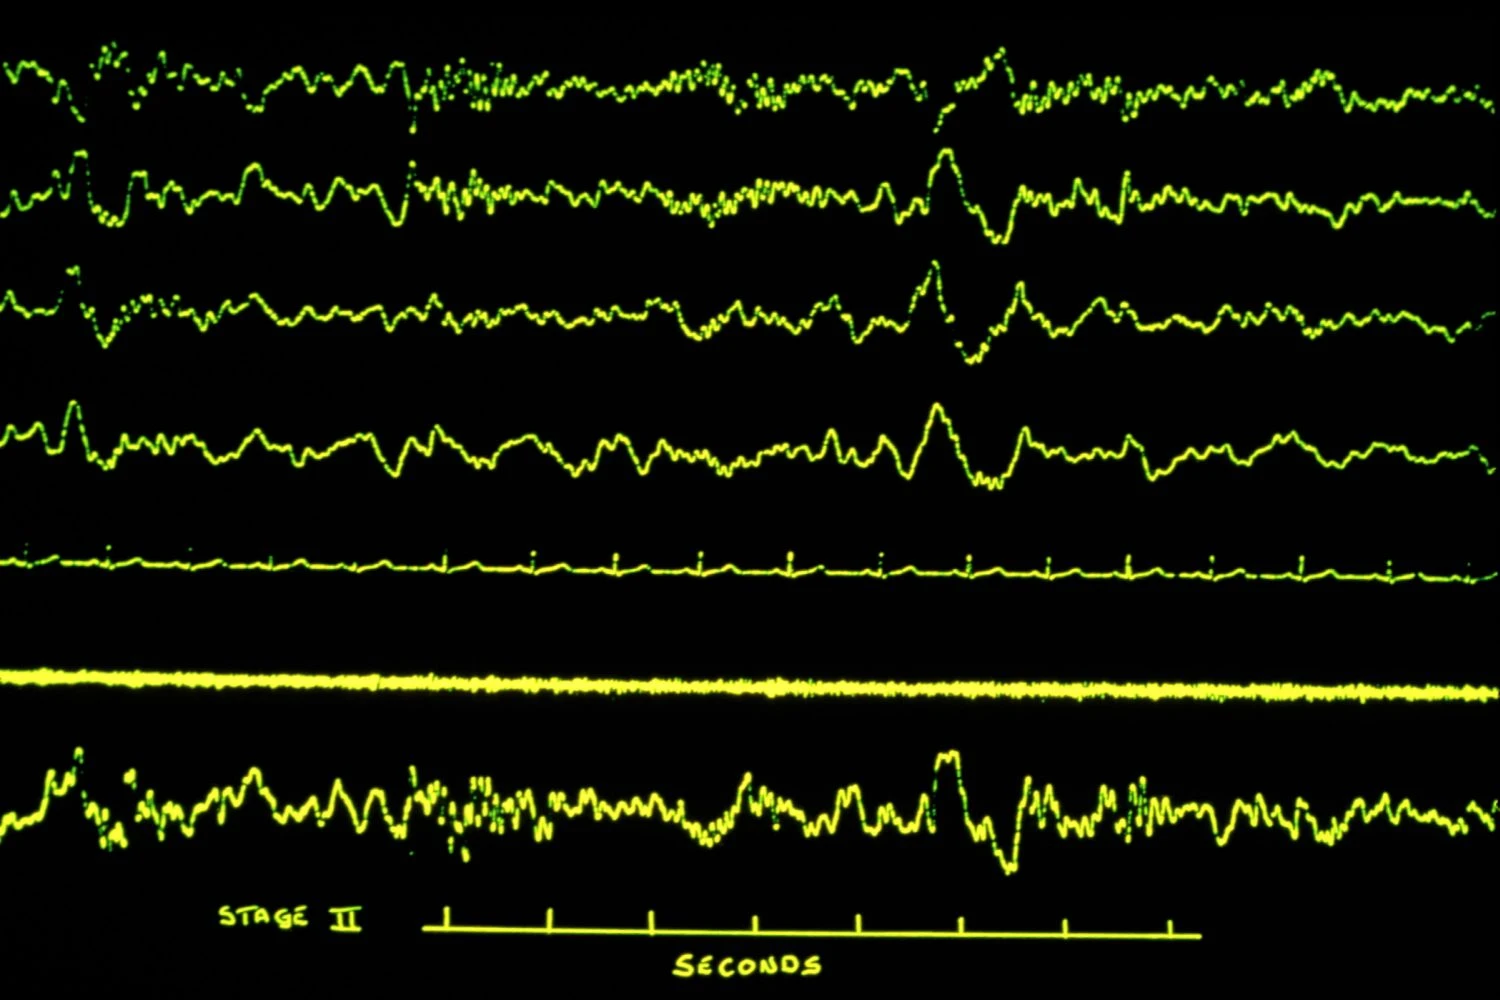

مرحله 2 خواب غیر REM

مرحله 2 خواب غیر REM. توضیحات تصویر در منبع اصلی موجود است.

این مرحله دوم خواب، با کاهش بیشتر ضربان قلب، فشار خون، سرعت تنفس و فعالیت عضلانی، آرامش بدن را ادامه می‌دهد. با این حال، حرکات چشم در این مرحله متوقف شده‌اند. به منظور کاهش بیشتر نیازهای انرژی، دمای بدن نیز حدود 0.5 تا 1 درجه سانتیگراد کاهش می‌یابد. یک EEG که در طول این مرحله انجام می‌شود، اغلب امواج K، یا امواج بلند و با ولتاژ بالا که تا 1 ثانیه طول می‌کشند، و دوک‌های خواب، یا دوره‌هایی از ولتاژ پایین و سنبله‌های با فرکانس بالا، را به عنوان نشانه‌های مشخصه نشان می‌دهد. به طور کلی، این مرحله حدود 10 تا 25 دقیقه طول می‌کشد.